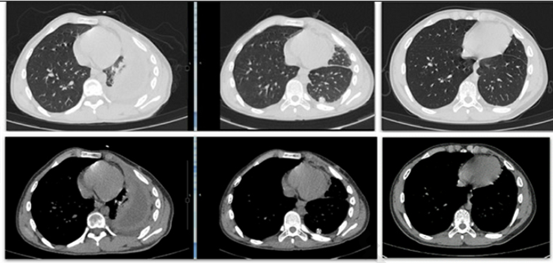

2、纤维脓性期(Ⅱ期) 脏层胸膜和壁层胸膜出现大量纤维素沉着,在脏层胸膜也就是肺的表面形成纤维素层,影响肺的复张,由于渗出液被回吸收,积液中蛋白质沉积,形成大小不等的蜂窝状分隔。渗出液变得粘稠,胸水中细胞数增多,多为淋巴细胞。

随着病程进展,渗出液逐渐由浆液性转为脓性,胸液中脓细胞及纤维蛋白增多,纤维蛋白逐步沉积于脏、壁胸膜表面形成纤维素层,影响肺的复张,由于渗出液被回吸收,积液中蛋白质沉积,形成大小不等的蜂窝状分隔。胸液特点是pH<7. 20,葡萄糖含量小于2. 2 mmol/L , LDH > 1000IU/ L 。初期纤维素膜附着不牢固,质软而易脱落。3、慢性脓胸期(Ⅲ期) 脏层胸膜和壁层胸膜在慢性炎症的刺激下逐渐增厚,形成增厚的纤维板,晚期新生毛细血管和成纤维细胞长入,机化,变硬,两层纤维板之间为脓腔,里面有肉芽组织和稠厚的脓液,及干酪样坏死物,膈肌表面也常为纤维板包裹。纤维板可嵌人肺组织中,使肺膨胀受到限制,损害肺功能并形成一个可能持续感染的脓腔。增厚的纤维板也可束缚肺和膈肌的表面,影响肺和膈肌的运动,导致不同程度的呼吸功能受损。一般的肺表面的脏层胸膜纤维板增厚程度要小于壁层纤维板增厚,有的壁层纤维板增厚超过3cm。壁层纤维板增厚,机化甚至钙化,纤维板收缩可引起肋间隙变窄,胸廓塌陷,对处于发育期的青少年患者可引起脊柱侧弯。